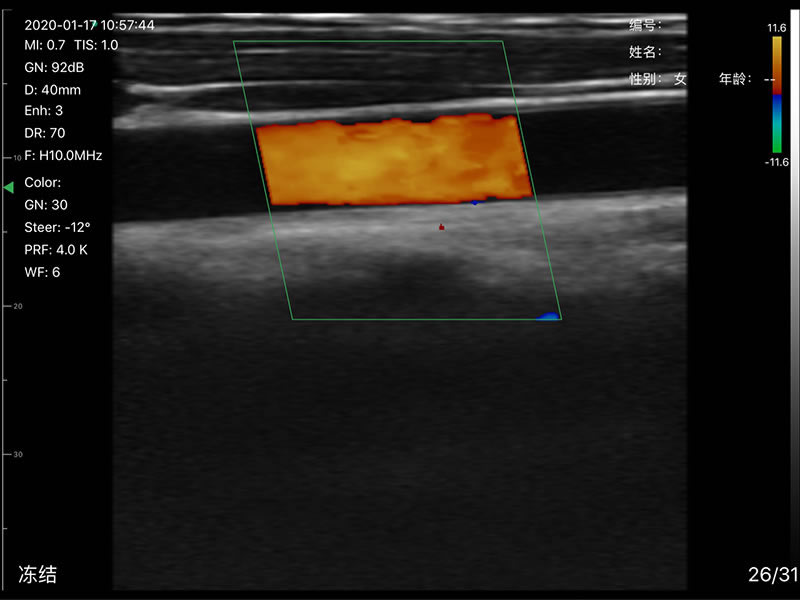

L40 Linear probe 7.5MHz/10.0MHz

• Display Depth: Convex 90/160/220/305mm, Linear 20/40/60/80mm